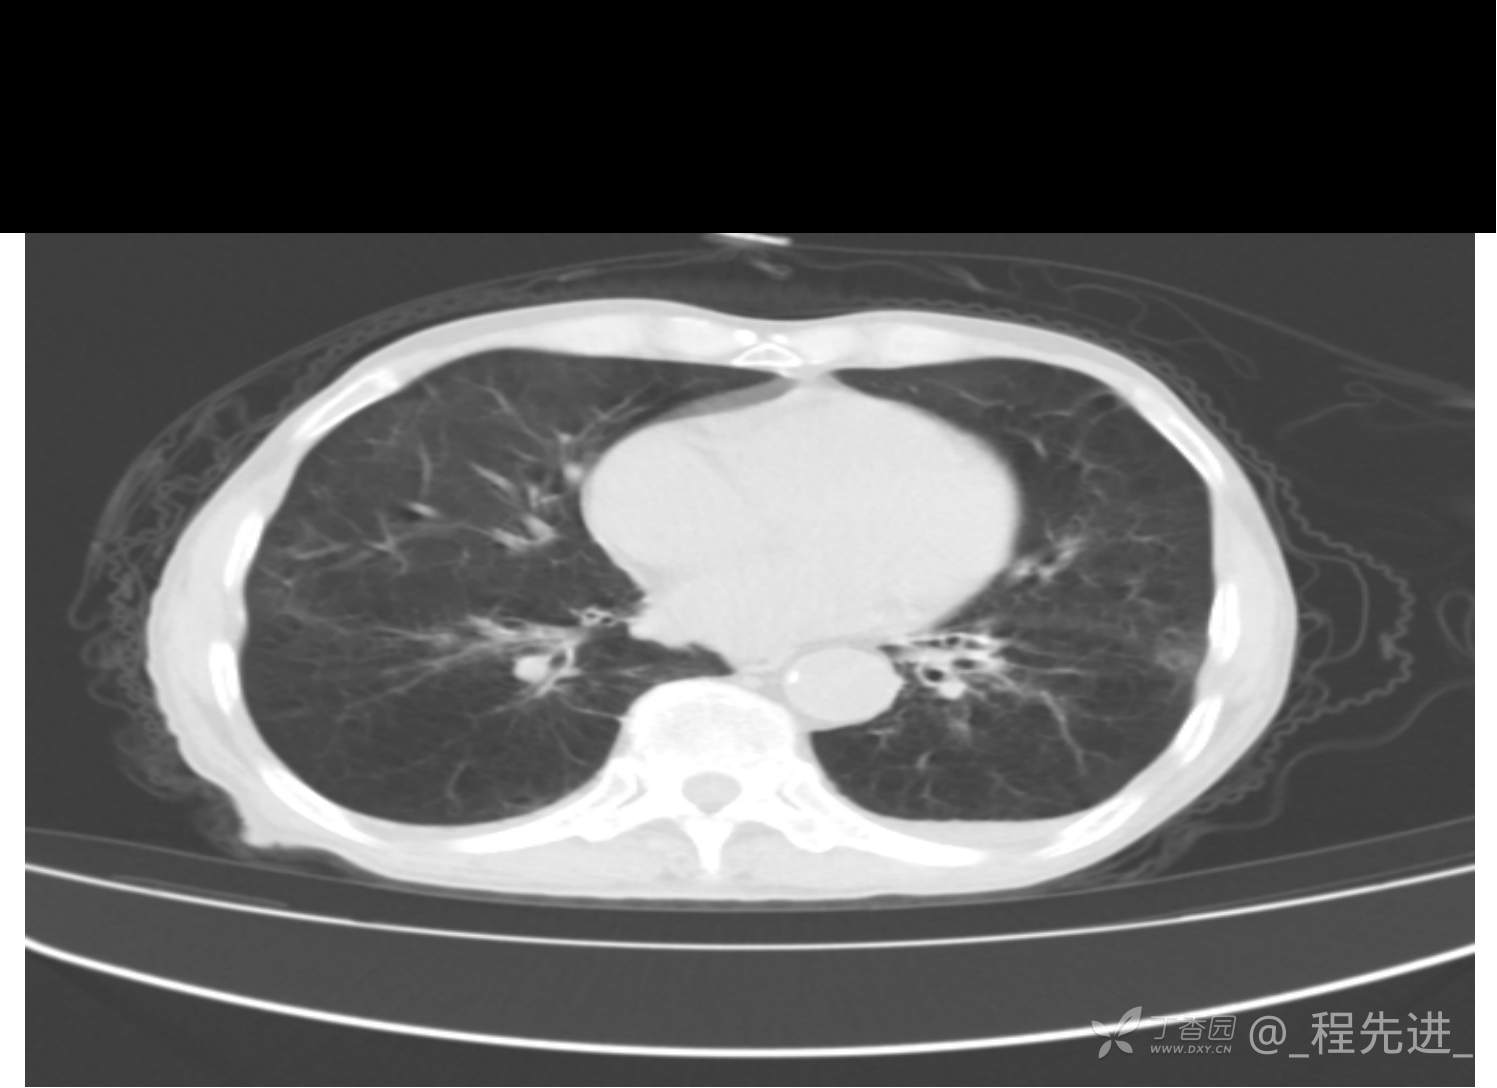

患者性别:男

患者年龄:81岁

简要病史:反复咳嗽、咳痰20余年,加重1周。两肺呼吸音低,可闻及散在干湿啰音。